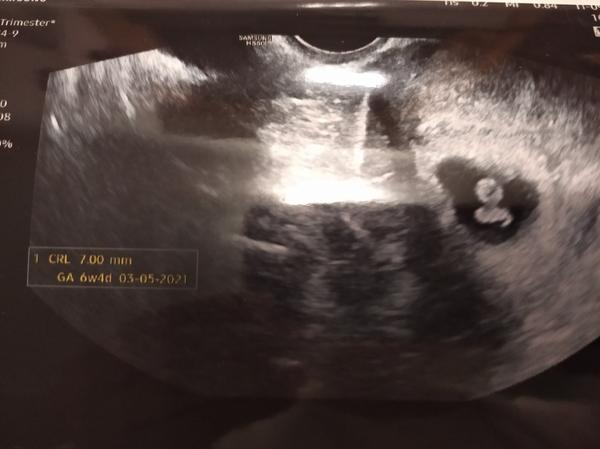

Já byla v pátek 6+4 a už i srdíčko.